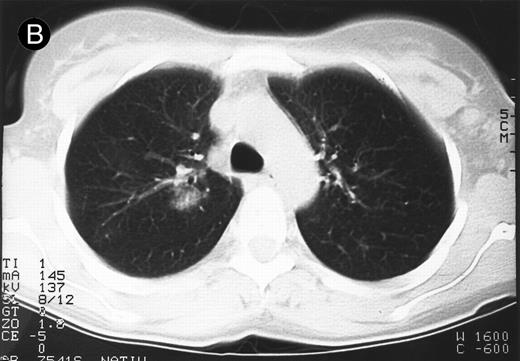

Response to therapy.In 15 of 15 evaluable patients, 1 CR and 1 PR with entire relief of B symptoms were observed after therapy with 64 mg/2 and 4 mg/m2, respectively, that lasted for 6 months and for 3 months, respectively. In addition, 3 MRs and 2 disease stabilizations (after documented preceding progressive disease) were observed, with 2 of them still ongoing after 10 and 11 months, respectively. One mixed response with a considerable reduction of a pulmonary mass (Fig 1) and left cervical lymph nodes but with growth of lymph nodes at distant sites was observed. No clear dose-response correlation could be established, although the CR occurred at the maximum dose administered (Table 2).

Response to HRS-3/A9 treatment of patient no. 7. Computed tomography (CT) scans of a pulmonary infiltration with HD in the right lung just above the tracheal bifurcation level is shown before (A) HRS-3/A9 therapy and (B) 5 weeks after the last BiMoAb infusion (4 mg/m2 × 4). The response was determined a mixed response because the partial response in the lung was accompanied by the simultaneous growth of peripheral lymph nodes.